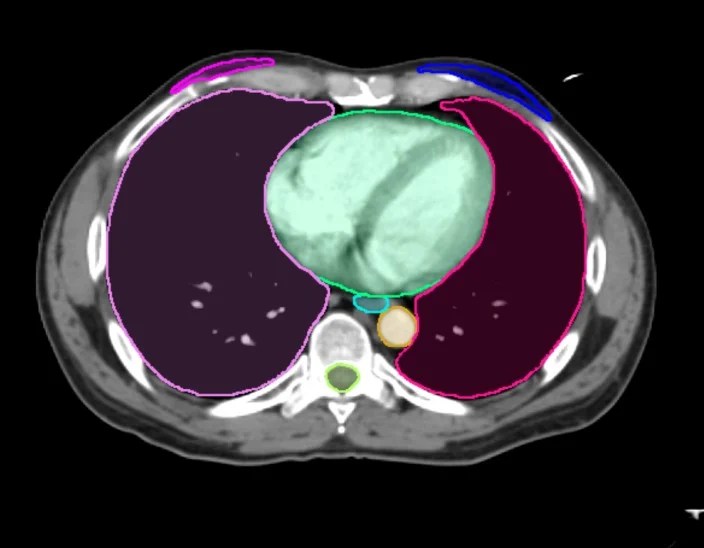

Auto-contouring is an ideal use case for deep learning algorithms because it is one of the most time-consuming clinical tasks. Contour ProtégéAI pushes the capabilities of auto-contouring forward. Deep learning algorithms optimized and automated by MIM make contouring more efficient without sacrificing accuracy.